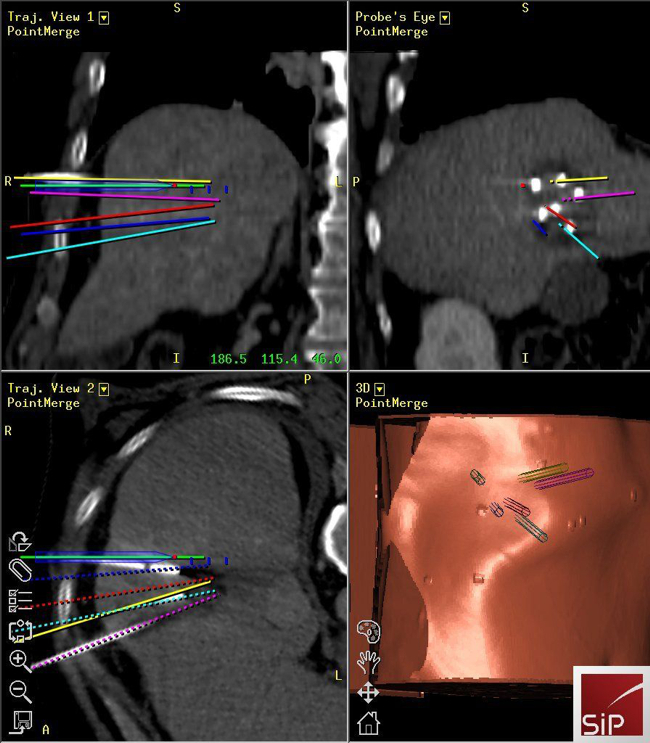

Interventional Oncology

Reto Bale

- Image-guided tumour ablation

- Stereotaxis

- Robotics

- Targeting

- Interventional oncology

Stereotactic ablation of liver tumours:

Radiofrequency ablation (RFA) allows local curative tumour treatment by inducing coagulation necrosis with a high-frequency alternating current. The major limiting factor of conventional US- and CT- guided percutaneous single probe ablation is the tumour size. Navigation systems allow for 3D-planning of multiple overlapping ablation zones on the CT datasets and precise transformation into the real patient. We developed the worldwide first aiming device for frameless stereotactic punctures and performed the first in man stereotactic radiofrequency ablation (SRFA) of a liver tumor in 2001. Meanwhile > 1000 patients with > 3000 liver tumors, most of them being inoperable, have successfully been treated at our department.